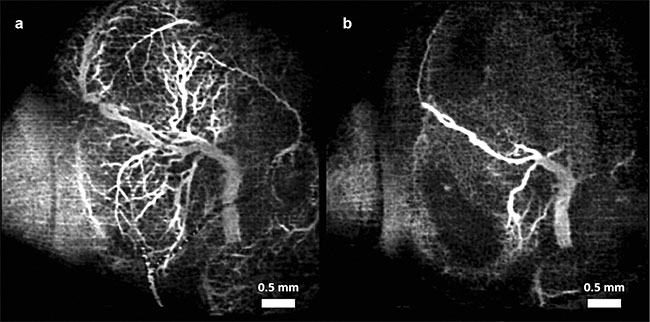

Figure 3. Vasculature changes in the embryonic brain before (a) and 45 min after (b) maternal exposure to synthetic cannabinoids (SCBs). Adapted with permission from Reference 12.

In recent studies, angiographic OCT was used to image murine fetal brain vasculature in utero10-12. A series of experiments documented changes in murine fetal brain vasculature minutes after maternal exposure to various drugs. Embryos of pregnant mice at embryonic day 14.5 were imaged. This period corresponds to the end of the first trimester and beginning of the second trimester in human development. Initial OCT imaging was performed, and the mother was administered the drug for the corresponding study. Subsequent measurements were taken of the embryo for a period of 45 min, at 5-min intervals.

For the nicotine experiments, nicotine at a dose of 1 mg/kg was used. This dose in mice is known to cause intrauterine growth restriction. Both the alcohol and nicotine were administered via intragastric gavage. For the SCB studies, CP-55,940 at a dose of 2 mg/kg, suspended in a compound of dimethyl sulfoxide (DMSO) (Alkamuls El 620: lactated Ringer’s solution at a ratio of 1:1:18), was sprayed onto the liver of the mother. CP-55,940 was used because it is a well-known and well-characterized compound in SCB research.

Speckle variance OCT (svOCT) and correlation mapping optical coherence angiography (cmOCA) are two types of angiographic OCT techniques that were used in the studies. While svOCT calculates the variance between multiple images taken at the same spatial location, cmOCA calculates the correlation coefficient between the images to capture any dynamic scatterers (such as blood in this case) in the specific location. These procedures are followed at multiple consecutive locations to obtain a vasculature map. Once the 3D vasculature maps were obtained, the maximum intensity projections (MIPs) were calculated to obtain 2D images.

Figures 1-3 show the vasculature in the fetal brain before and after maternal exposure to ethanol, nicotine, and SCBs, respectively.

In all three cases, when compared to placebo groups, a drastic reduction in vessel diameter was observed within 45 min of maternal exposure, demonstrating the possibility that all three teratogens act as a vasoconstrictor on the fetal brain. Such constriction could have a drastic effect on normal brain development.